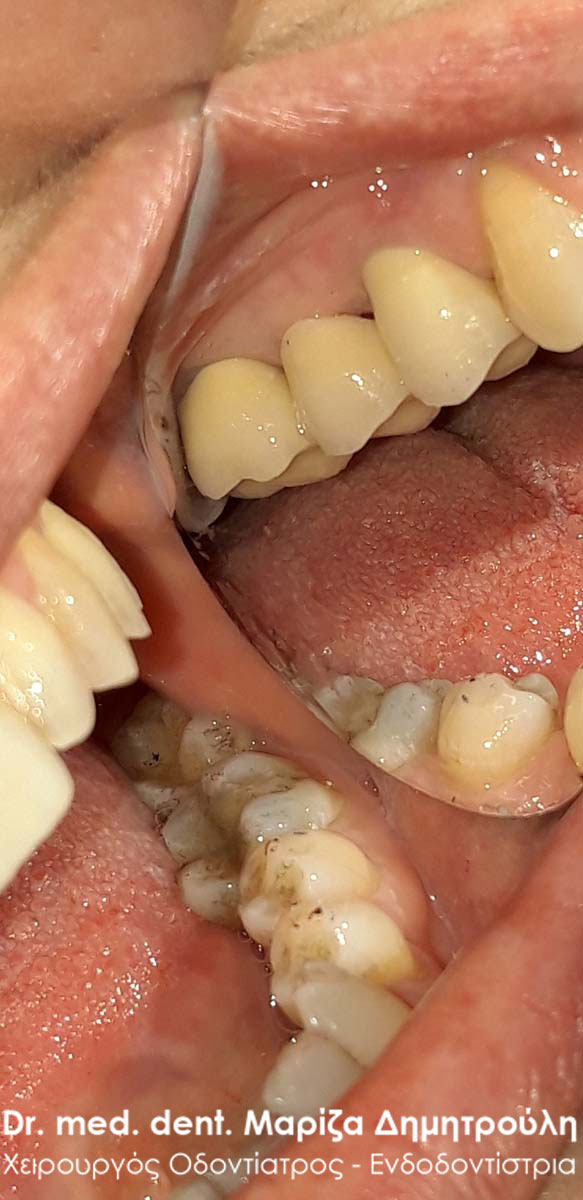

Περιστατικό – Στεφάνη / θήκη δοντιού

Ο ασθενής επισκέφτηκε το ιατρείο καθώς έσπασε ο άνω αριστερός προγόμφιος. Το συγκεκριμένο δόντι είχε μία παλία απονεύρωση δοντιού, η οποία περιοδικά έδινε συμπτώματα πόνου στον ασθενή. Μετά την κλινική και ακτινογραφική εξέταση του δοντιού αποφασίστηκε η επανάληψη της απονεύρωσης δοντιού και η προστασία του δοντιού με θήκη.

ΠΡΙΝ – Φωτογραφία πριν την αφαίρεση της παλιάς απονεύρωσης του δοντιού

Ακτινογραφική εικόνα του δοντιού πριν την επανάληψη της απονεύρωσης

Ακτινογραφική εικόνα του δοντιού μετά την επανάληψη της απονεύρωσης